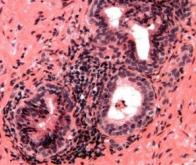

Une étude internationale coordonnée par les Professeurs Selth (université Flinders en Australie) et Xie (université de Chine méridionale) a découvert que le cancer de la prostate dépend de deux enzymes clés, PDIA1 et PDIA5, pour survivre et résister aux traitements. Le blocage de ces enzymes entraîne l'effondrement du récepteur des androgènes, ce qui détruit les cellules cancéreuses et potentialise l'effet de médicaments comme l'enzalutamide. Ces enzymes perturbent également le système énergétique du cancer, l'attaquant sur plusieurs fronts. Des scientifiques ont identifié une faille majeure dans les cellules cancéreuses de la prostate en découvrant deux enzymes, PDIA1 et PDIA5, qui permettent à la maladie de survivre et de résister au traitement. Le blocage de ces enzymes déstabilise le récepteur des androgènes, principal moteur du cancer de la prostate, entraînant une réduction de la tumeur et la mort cellulaire.

Selon les chercheurs, PDIA1 et PDIA5 agissent comme des protecteurs moléculaires du récepteur des androgènes (RA), une protéine qui stimule la croissance du cancer de la prostate. Lorsque ces enzymes sont bloquées, le RA perd de sa stabilité et se désagrège, entraînant la mort des cellules cancéreuses et la réduction des tumeurs, aussi bien in vitro que chez les animaux.